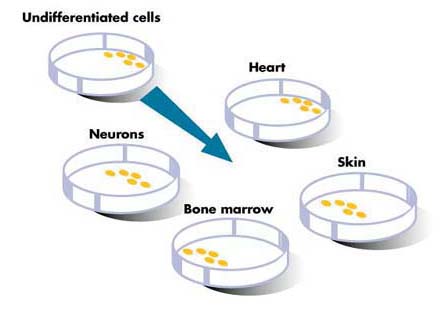

Получены стволовые клетки обезьян без использования жизнеспособных эмбрионов